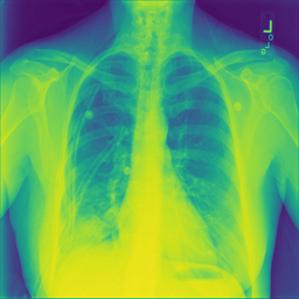

Figure 5: Some Sample Images of Actual Class Predicted correctly by TL Model

The Figure5 demonstrates how LIME explains the model’s correctly classified prediction of a chest X-ray. The true label is Viral Pneumonia and the model predicted Viral Pneumonia, correctly classifying the image. In the first set, LIME highlighted areas corresponding to Viral Pneumonia in green, while marking other classes in red. In the second set, LIME highlighted areas suggesting Normal in green, with other classes in red. In the third set, LIME highlighted regions indicating COVID in green, and other classes in red. In the fourth set, LIME highlighted areas associated with Lung Opacity in green, with other classes in red.LIME functions by graphically emphasizing the particular areas inside an image that have substantially influenced the model’s prediction.

In the initial image, the green area for Viral Pneumonia is larger than the green areas in the other three images. This is why the model is influenced by these features and predicted Viral Pneumonia. This approach helps maintain transparency between the model and its predictions, allowing us to understand the specific reasons behind the model’s decisions. By examining these highlighted areas, we can see how the model is influenced by certain features, ensuring that we know exactly why the model predicted a particular class. This transparency is crucial for validating the model’s accuracy and reliability.